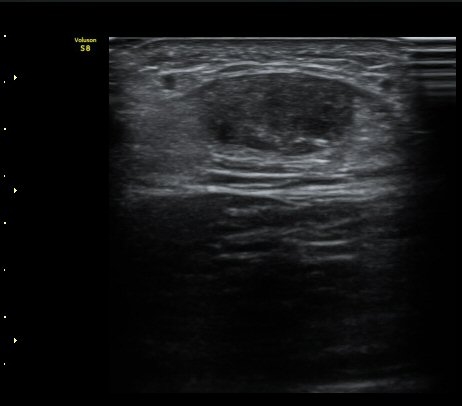

[¹ß¸ñ] ¾ÆÅ³·¹½º ÈûÁÙ ÆÄ¿­ÀÇ ÃÊÀ½ÆÄ Áø´Ü

ÁÂÃø ¹ß¸ñÀÇ ÅëÁõ(2ÁÖ)

2ÁÖ Àü ¹èµå¹ÎÅÏÇÏ´Ù°¡ ¹ß¸ñÀÇ ÅëÁõÀÌ ¹ß»ýÇÏ¿© Ÿº´¿ø¿¡¼­ ÃÊÀ½ÆÄ°Ë»ç µî ½ÃÇàÇÏ°í ºÎ¸ñ°íÁ¤ ÈÄ ¹°¸®Ä¡·á À§ÇØ ³»¿ø

¾ÆÅ³·¹½º°Ç ºÎÁ¾ ¹× ¾ÐÅë, ´Éµ¿Àû ¹ß¸ñ ¹ß¹Ù´ÚÃø ±¼°ñ G 1, thomson test(+).

ÃÊÀ½ÆÄ °Ë»ç